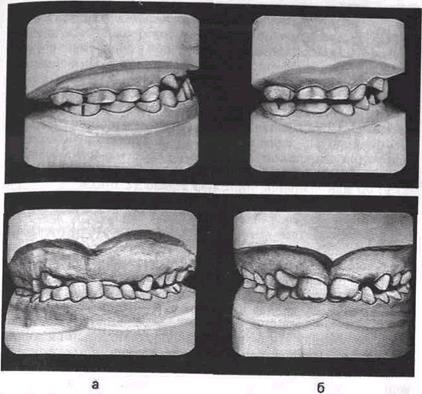

Лицевые признаки нарушений при мезиальном прикусе зубоальвеолярной формы следующие Верхняя губа по отноше­нию к нижней западает, подносовая складка углублена, розо­вая кайма нижней губы широкая При глубоком резцовом перекрытии нижняя часть лица укорочена, в связи с чем нижняя губа утолщена (рис 16.25) При увеличенных нижнечелюстных углах и открытом прикусе нижняя часть лица удлинена, губы смыкаются с напряжением, ротовая щель нередко зияет. Если мезиальный прикус сочетается со смещением нижней челюсти вперед, то лицевые признаки нарушений бывают выражены резче При этом в обратном перекрытии могут находиться не только резцы, но и клыки, иногда первые премоляры Нижние резцы обычно отклоняются вестибулярно, вследствие чего между ними появляются тремы или они оказывают давление на верх­ние резцы, усиливая их небный наклон. В боковых участках зубных дуг нередко наблюдается вестибулярный перекрестный прикус. Если пациент может сместить нижнюю челюсть назад до краевого смыкания резцов и при этом соотношение первых постоянных моляров становится характерным для нейтрального прикуса, то диагностируют зубоальвеолярную форму мезиаль-

рис 16 25 Изменение формы профиля лица (а, 6) в результа­те ортодонтического лечения мезиального прикуса со смеще­нием нижней челюсти вперед, обусловленного вредной привыч­кой сосания языка (в)

ного прикуса со смещением нижней челюсти вперед. Та­кую клиническую функцио­нальную пробу используют при дифференциальной диаг­ностике зубоальвеолярной и гнатической форм мезиально­го прикуса.